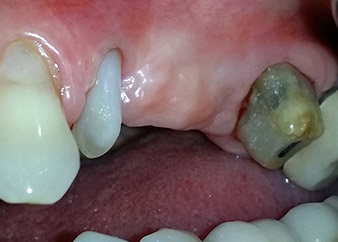

perte totale d'os et d'attache

Fig. 2 et 3 : Après élévation des lambeaux, un mois après le retraitement endodontique et le démarrage du traitement parodontal global, la racine de la dent 24 présentait une perte totale d'os et d'attache.

Nous avons toutefois maintenu notre projet initial de conservation des deux dents comme piliers temporaires d'un bridge pendant la période de six mois nécessaire à l'ostéointégration des implants. À la prochaine incision, la situation devrait être réétudiée. Premièrement, afin de gérer le problème endoparodontal, la surface de racine restante a été soigneusement débridée à l'aide d'un équipement piézoélectrique (Piezomed, W&H, utilisé avec l'insert en forme de spatule S1, initialement conçu pour limer la paroi sinusienne latérale) (Fig. 4).